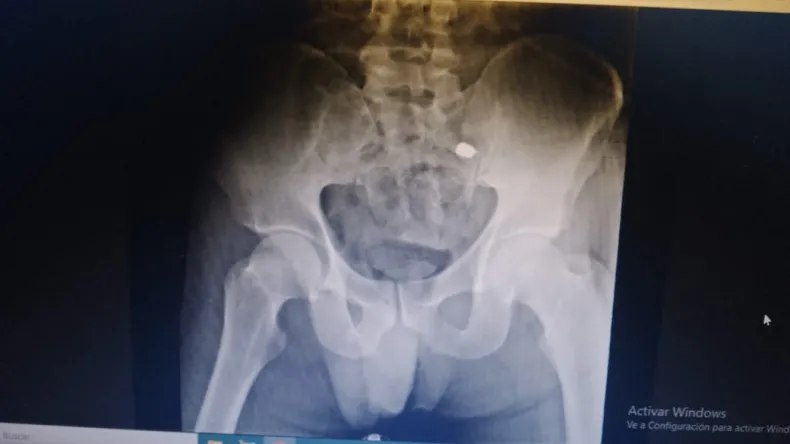

De acuerdo a los primeros datos suministrados por fuentes judiciales, Rivero, con domicilio en el Lote Hogar N.º 11, fue alcanzado por dos disparos: uno en la pantorrilla, con orificio de entrada y salida, y otro en la cadera. Pese a las dos heridas, se encuentra consciente y fuera de peligro.